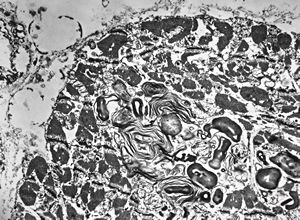

F, 25y. | metachromatic leukodystrophy … n. suralis